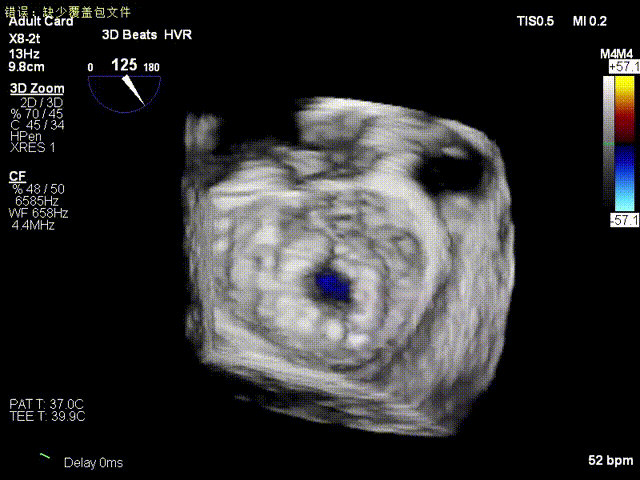

术前食道超声示二尖瓣重度关闭不全,重度反流;

术前食道超声

术前食道超声3D